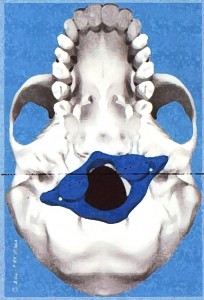

Az öreglyuk melletti bütykök elhelyezedése nem szimmetrikus, deformálódtak az idegek, erek csontos kijáratai és maga az öreglyuk is. Megdöbbentő bizonyítékot találtunk az atlasz koponyaalpot torzító elfordulására. Egy idős ember koponyáját alaposan megvizsgálva a következő tudományos bizonyítékot leltük: Az elfordult atlasz torzította és csontos átépülésre késztette a koponyaalap fontos alkotórészeit: az atlasszal ízesülő bütyköket, a koponyaalapról kilépő csontos csatornákat, […]]]>

Az öreglyuk melletti bütykök elhelyezedése nem szimmetrikus, deformálódtak az idegek, erek csontos kijáratai és maga az öreglyuk is. Megdöbbentő bizonyítékot találtunk az atlasz koponyaalpot torzító elfordulására. Egy idős ember koponyáját alaposan megvizsgálva a következő tudományos bizonyítékot leltük: Az elfordult atlasz torzította és csontos átépülésre késztette a koponyaalap fontos alkotórészeit: az atlasszal ízesülő bütyköket, a koponyaalapról kilépő csontos csatornákat, […]]]>

Elbillent Atlasz A Magyar AtlasPROfilax Társaság hivatalos honlapja és a specialisták megtekinthetők a http://atlaszprofilax.com honlapon. A világ 30 országában mintegy 350 specialista jogosult alkalmazni ezt a különleges eljárást, amit a svájci René Claudius SCHÜMPERLI dolgozott ki 1993-1996-ig. Az ATLASPROFILAX® egy speciális lágyrész wellness-masszázs kezelés, ami az első nyakcsigolya normális pozícióba való visszatérését teszi lehetővé. A feltaláló a világon elsőként észlelte […]]]>

Elbillent Atlasz A Magyar AtlasPROfilax Társaság hivatalos honlapja és a specialisták megtekinthetők a http://atlaszprofilax.com honlapon. A világ 30 országában mintegy 350 specialista jogosult alkalmazni ezt a különleges eljárást, amit a svájci René Claudius SCHÜMPERLI dolgozott ki 1993-1996-ig. Az ATLASPROFILAX® egy speciális lágyrész wellness-masszázs kezelés, ami az első nyakcsigolya normális pozícióba való visszatérését teszi lehetővé. A feltaláló a világon elsőként észlelte […]]]>